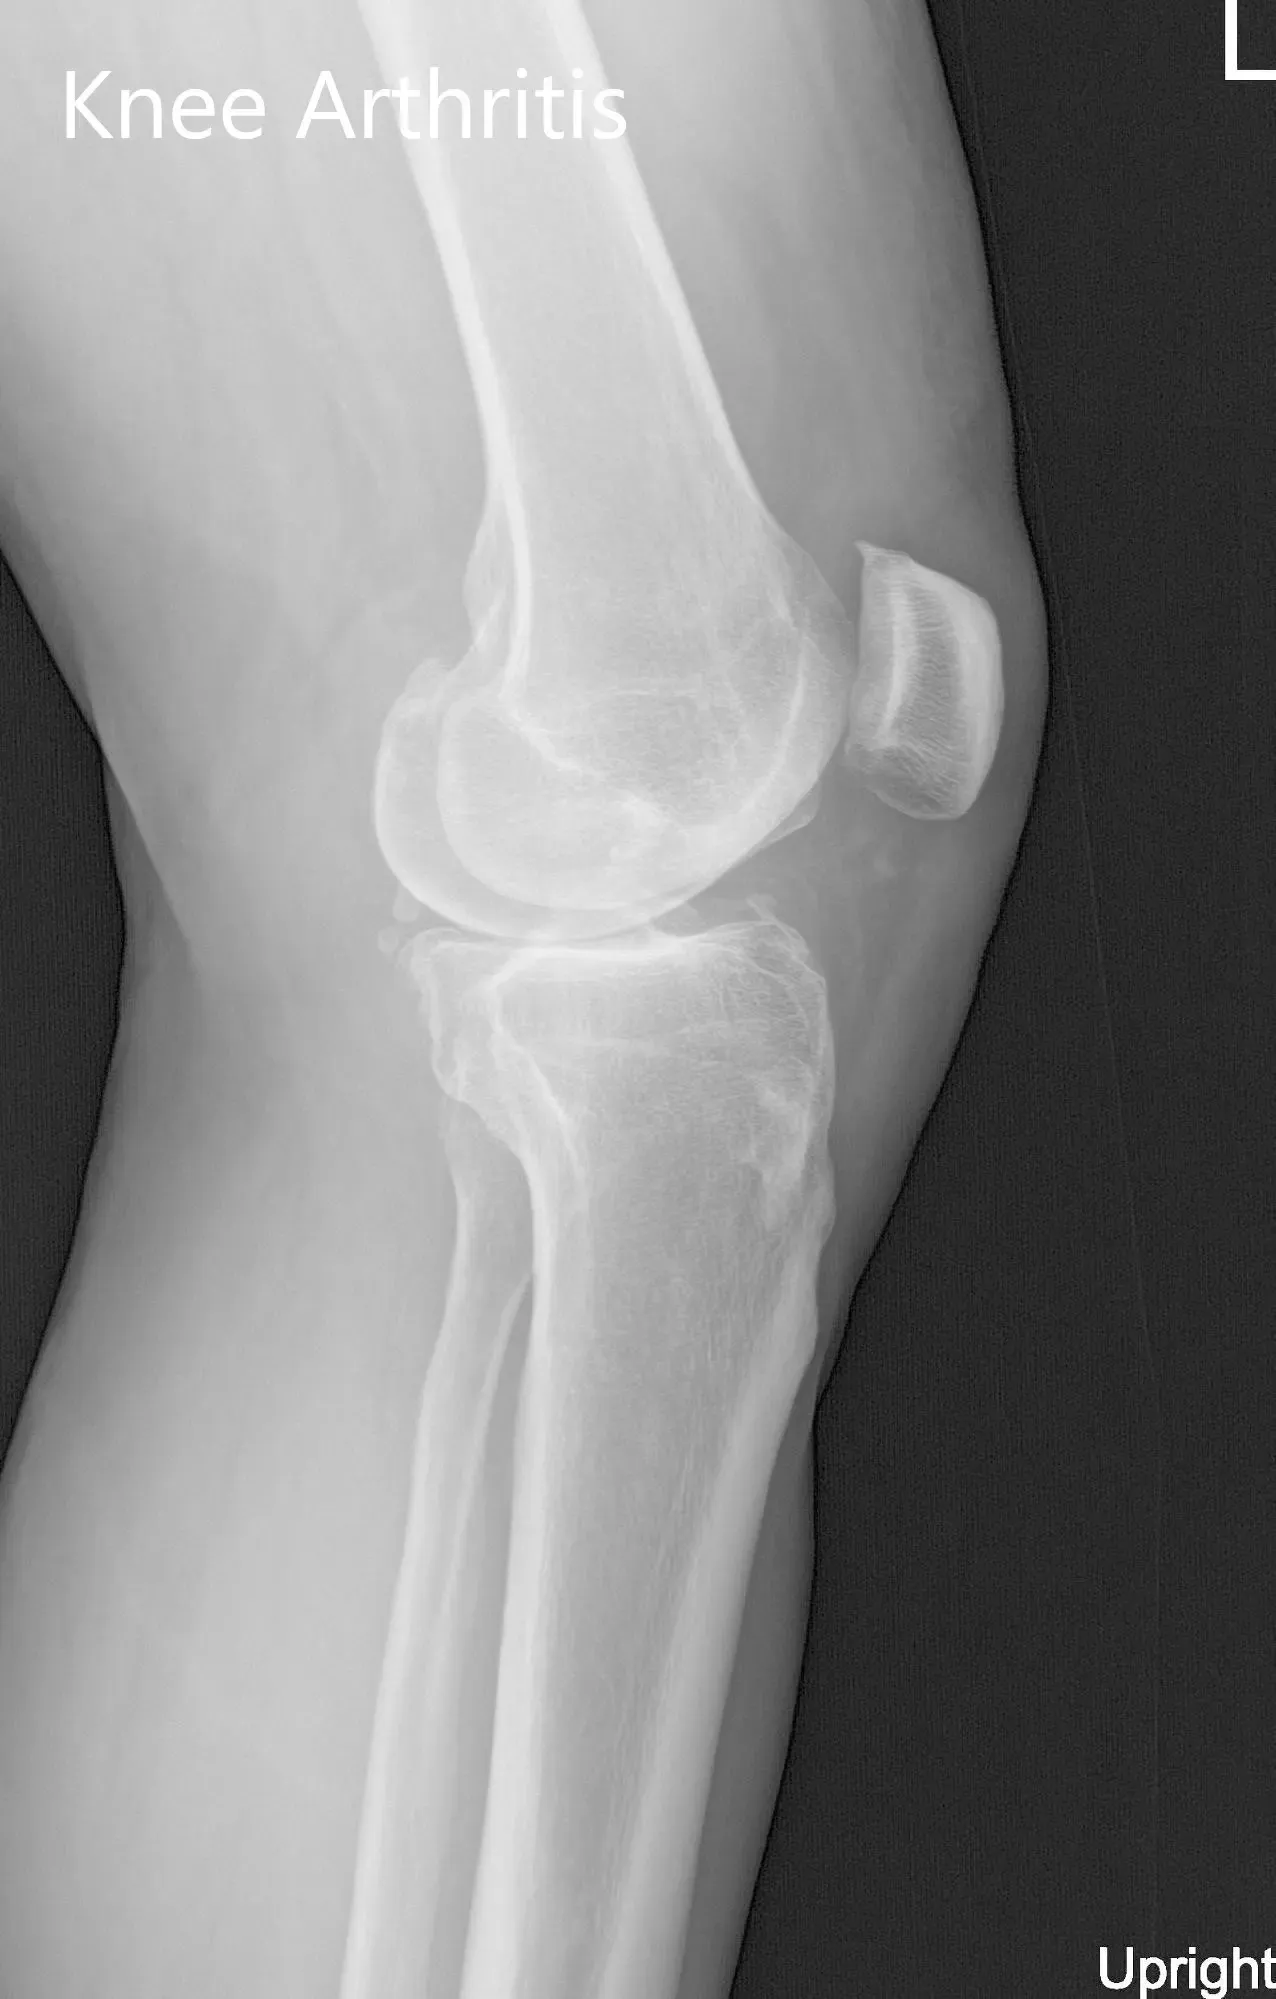

Her physical examination revealed mild knee swelling with a genu varus deformity. She had an antalgic gait with a decreased stance phase on the left side. There were no scar, sinuses or erythema on visible inspection. Palpation revealed medial joint line tenderness and medial patellar facet tenderness with copious joint crepitus on range of motion. End flexion was painful with no contracture. Imaging studies revealed tricompartmental osteoarthritic degenerative changes of the left knee.

Preoperative X-ray of the left knee showing AP and lateral views

Preoperative X-ray of the left knee showing AP and lateral views.